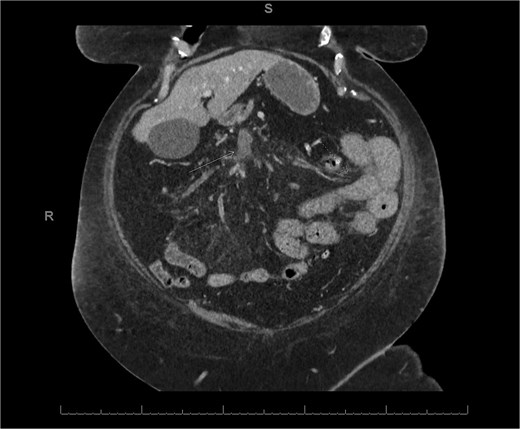

A 76-year-old female with a 3-day history of left upper abdominal pain, vomiting, and haematochezia. Her history included pulmonary embolism, multiple deep vein thromboses, with no ongoing anticoagulation, and an open partial colectomy for complicated diverticulitis a decade earlier. On admission, she was afebrile but tachycardic and showed localized tenderness in the left hypochondrium. Laboratory revealed leucocytosis with a white blood cell count (WBC) of 12 G/L, elevated C-reactive protein (CRP) of 46 mg/L, and hyperlactatemia of 2.6 mmol/l. Enhanced computed tomography (E-CT) revealed jejunal venous ischemia in the left upper quadrant, secondary to extensive porto-mesenteric thrombosis with reduced bowel wall enhancement, distention, and free intraperitoneal fluid (Fig. 1). She was managed conservatively with unfractionated heparin (UFH) with a bolus of 5000 U/l followed by 30 000 U/l/24 h (target INR 0.35–0.7), Piperacillin-Tazobactam, and bowel rest. After 48 h of monitoring in the intensive care unit (ICU), she exhibited marked biological and clinical improvement. E-CT on the third day showed restored bowel wall enhancement and stable porto-mesenteric thrombosis (Fig. 2). She was discharged on therapeutic low molecular weight heparin (LMWH) with enoxaparin sodium 120 mg every 12 h. At the 3-month follow-up, E-CT revealed near-complete thrombus resolution, without intestinal sequelae (Fig. 3).

Three-month E-CT of the first patient showing nearly complete thrombosis resolution, with no signs of intestinal distress.